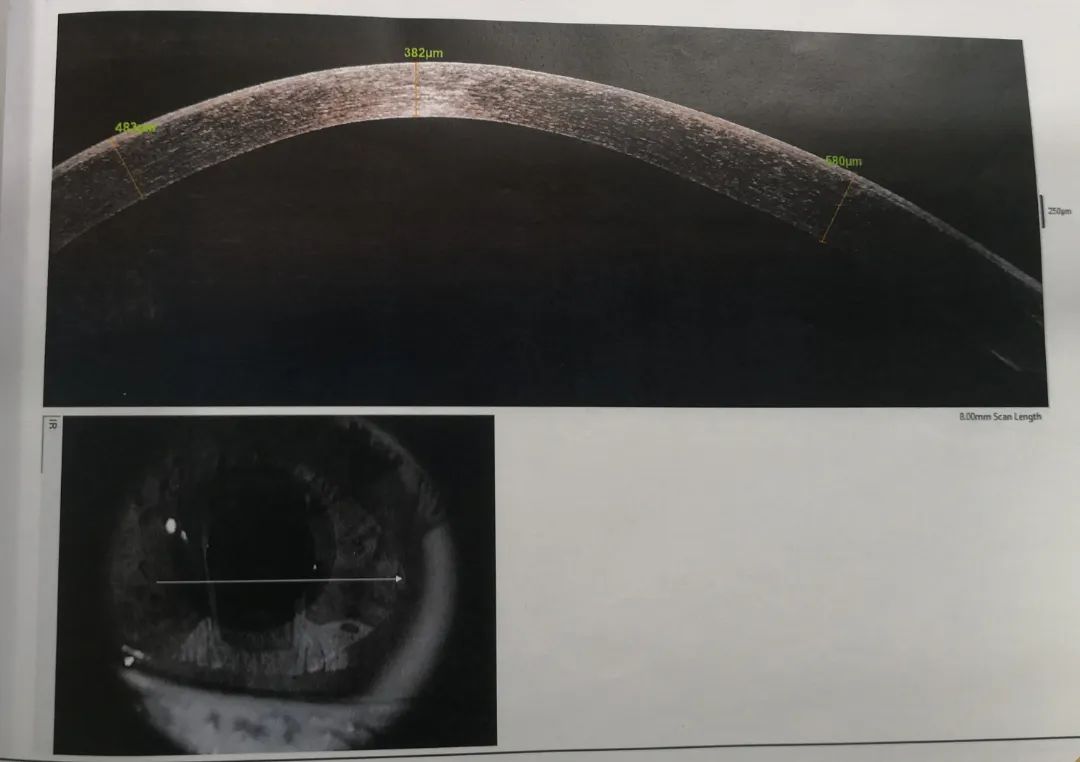

小雨重新回憶起之前的診治經歷,確定此前的檢查中并沒有圓錐角膜的檢查,羅順榮副主任為她完善了相關檢查。檢查結果顯示,小雨左眼還是圓錐角膜初期,但右眼已經是圓錐角膜的完成期,左眼角膜厚度為489μm,而右眼僅剩下382μm。